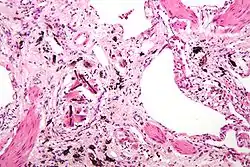

![]() صورة مكبرة عن السحار الاسبست( مع وجود أجسام حديدية)، وهو نوع من تغبر الرئة. صبغة H&E. صورة مكبرة عن السحار الاسبست( مع وجود أجسام حديدية)، وهو نوع من تغبر الرئة. صبغة H&E. | |